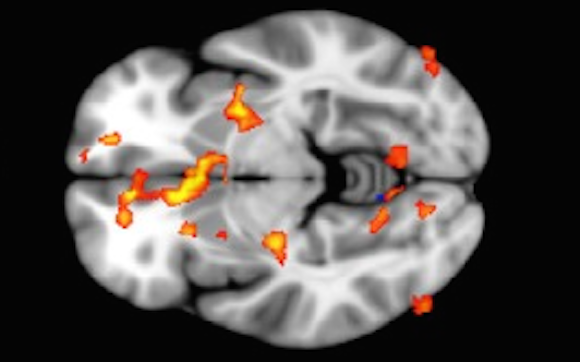

F1.large_1000.jpg

Recent developments in neuroscience have liberated both contemplative and psychedelic practices, which have been used for thousands of years to transcend human suffering.

Similar brain activity has been found in experienced practitioners of meditation and those under the influence of psilocybin.

In this article, I hope to open a door for you to engage your curiosity and continue down the rabbit hole to a more complex understanding of how the self is generated, and how this separation is destroyed.

Although subjective experiences may differ, objective data can be obtained from the activity of different brain regions.

We can then match the activity of different brain areas with previous research on the behaviour of those with deficits in said region to better understand the function of the structures involved (e.g. when the amygdala and hippocampal neurons fire synchronously, we interpret this as the individual becoming emotionally charged with anger/fear while recalling a traumatic experience).

To understand how the brains of meditators and psychonauts are undergoing similar changes, we must understand a recent development in neuroscience related to our “internal chatter” and perception of self in relation to other and time[1]: the Default Mode Network (DMN)

The DMN concept comes from an emergent body of evidence demonstrating a consistent pattern of deactivation across a network of brain regions that includes precuneus/posterior cingulate cortex (PCC), medial prefrontal cortex (MPFC) and medial, lateral and inferior parietal cortex; that occurs during the initiation of task-related activity (Raichle et al., 2001).

When psilocybin was administered via IV doses to subjects, and blood flow was measured to these DMN control areas, something very interesting occurred.

Blood flow to the PCC was diminished, and a decrease in the positive coupling between the mPFC and the PCC was observed.

Furthermore, blood flow to the PCC was inversely related to the psychedelic and mystical effects.

Not surprisingly, we also see an increase in the activity of the ACC.[5]

We see the same neural correlates of the experienced meditator group and in the psilocybin group! Interestingly enough, we could now predict what the psilocybin experience would be like if we’d never polled a subject.